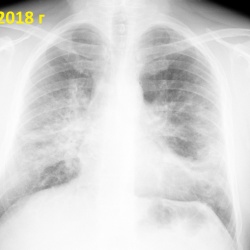

Добрый день. Подскажите пожалуйста как описать тяжи в левом легком? Что это может быть ? из анамнеза - только известно что есть крупный шрам под левой грудью